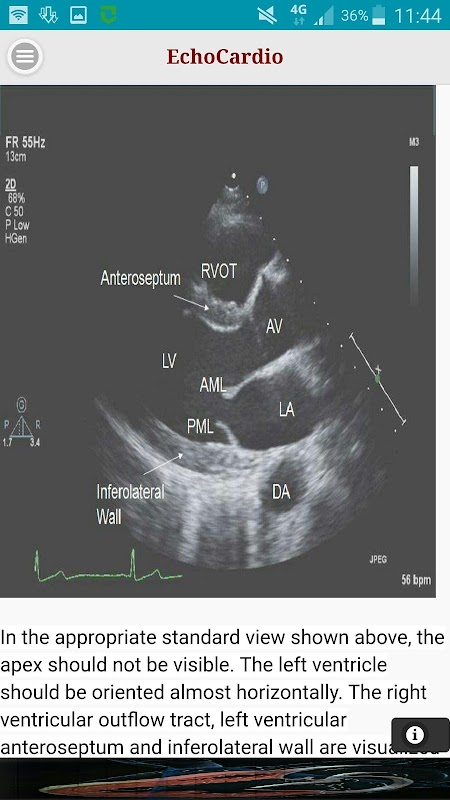

Paraesternal eje largo